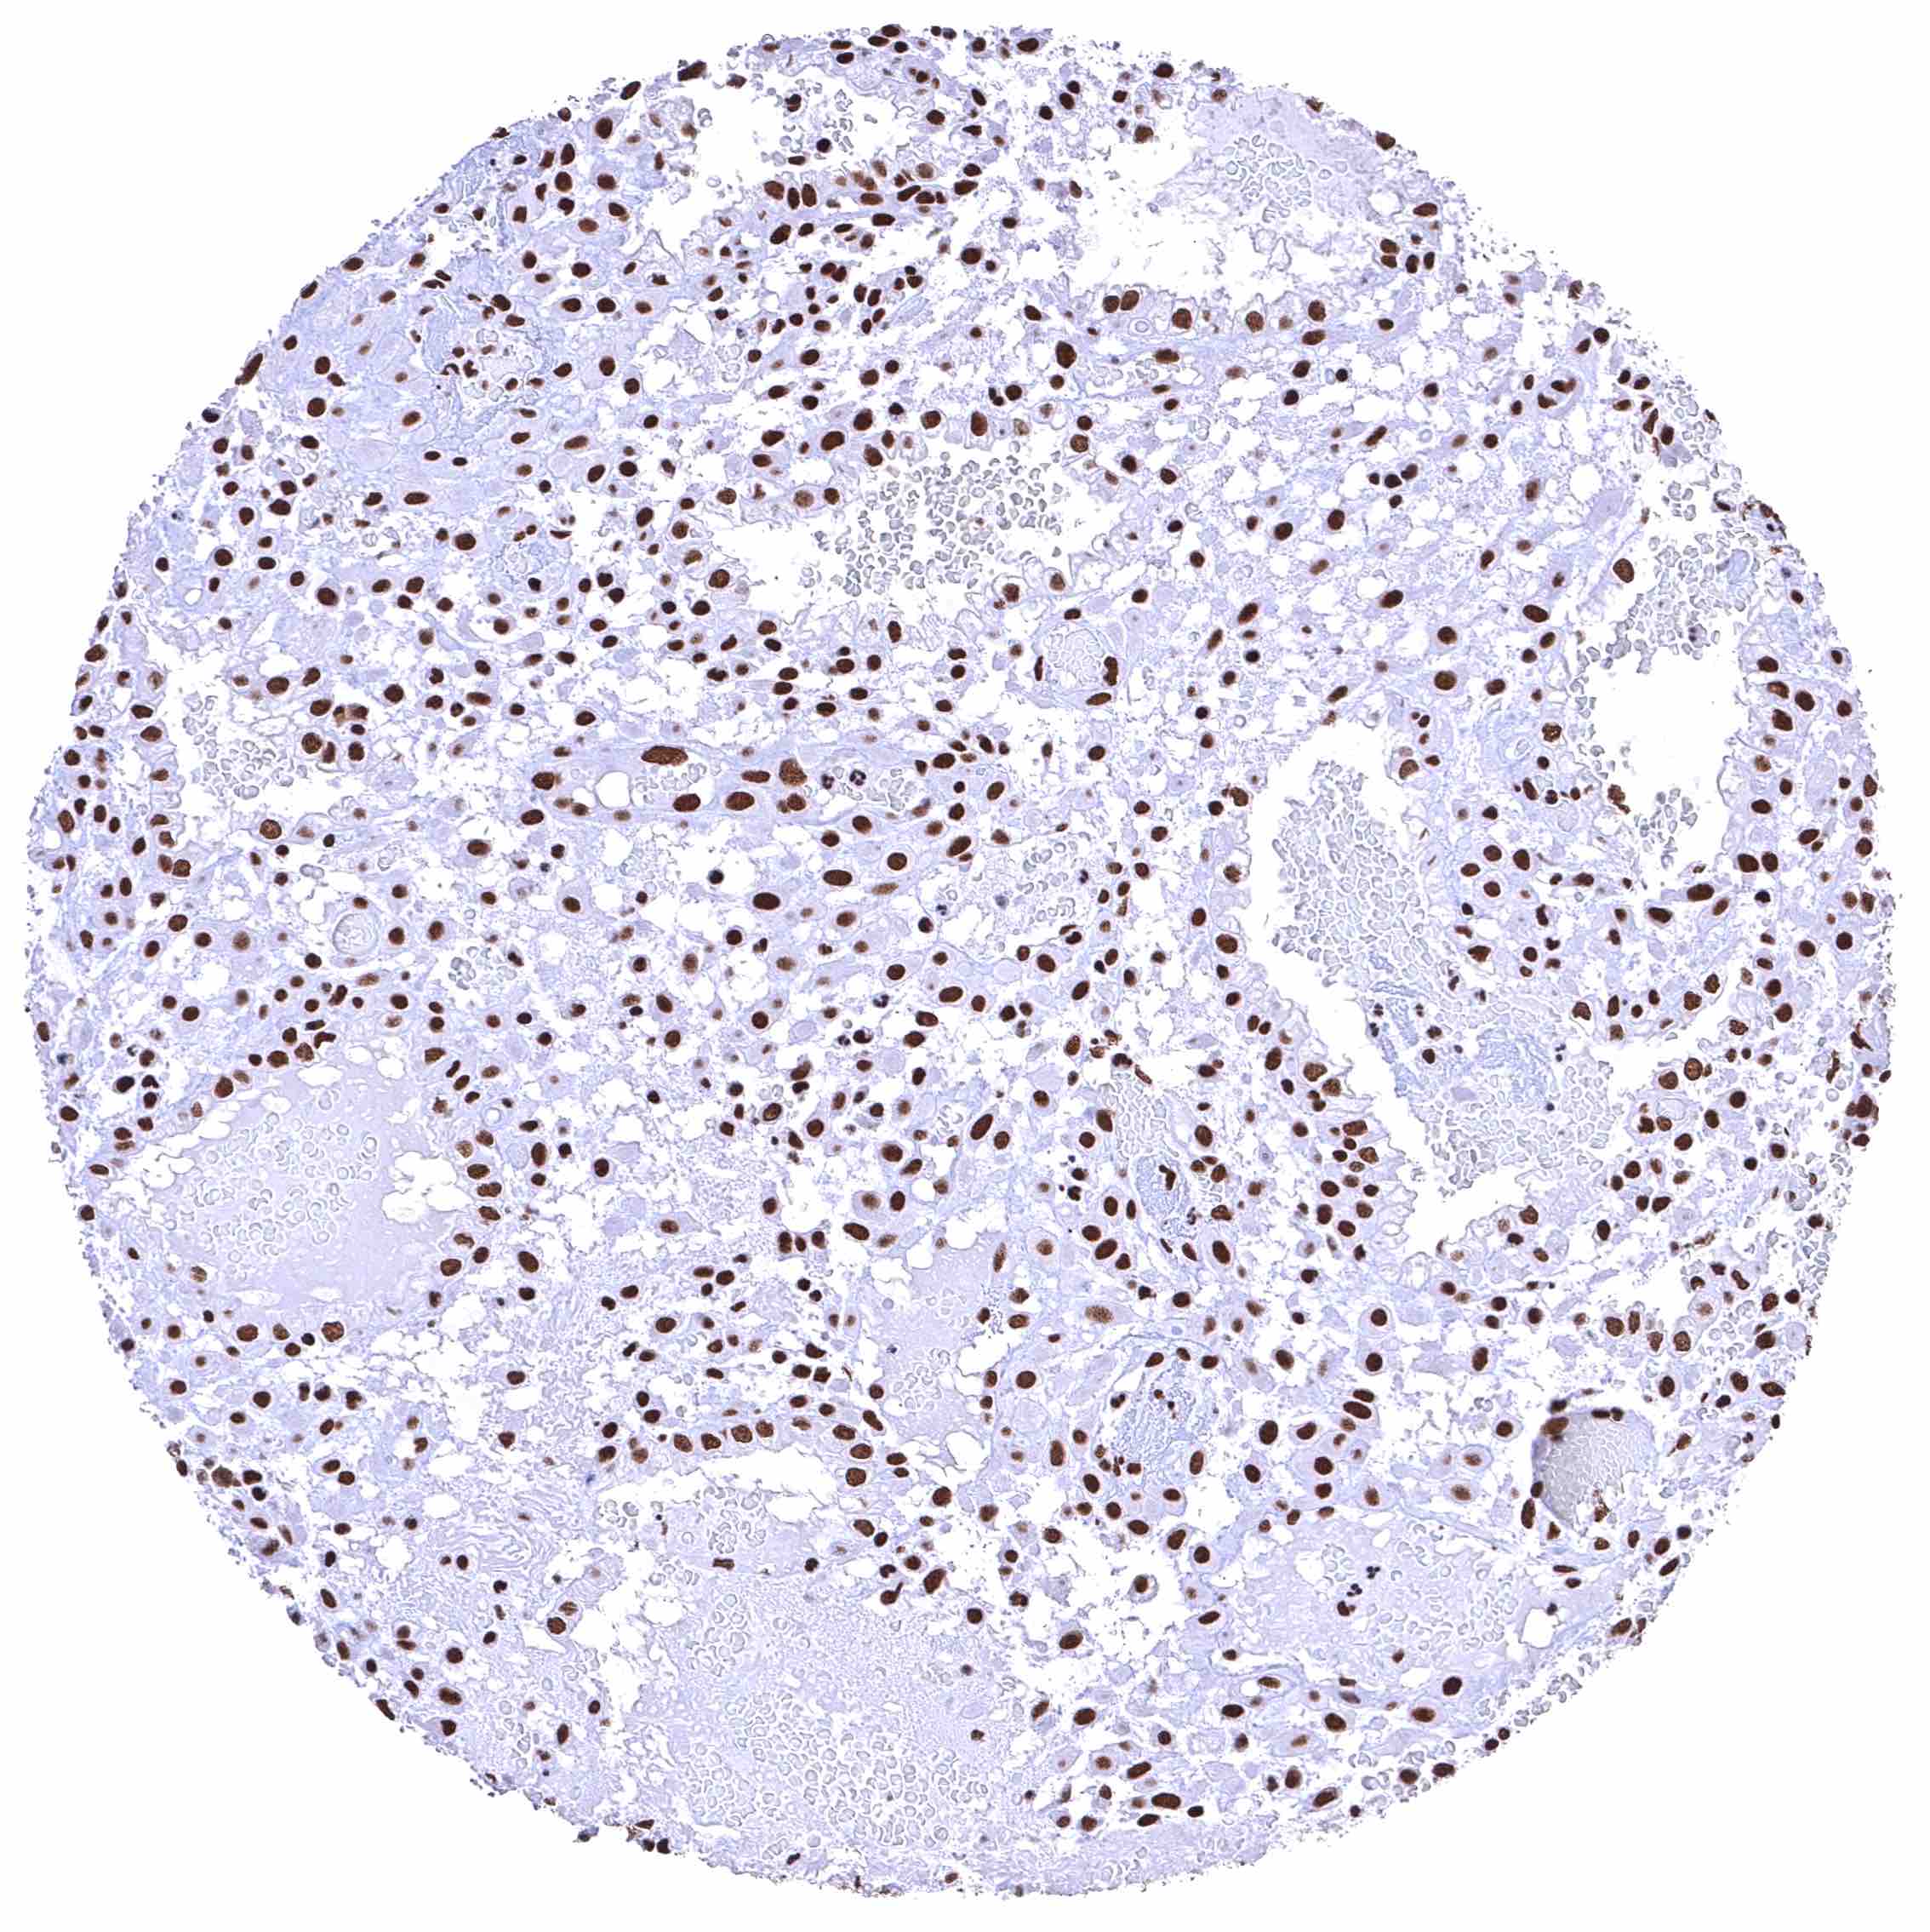

Placenta, mature – BRD4 staining is either absent or massively reduced in the syncytiotrophoblast.